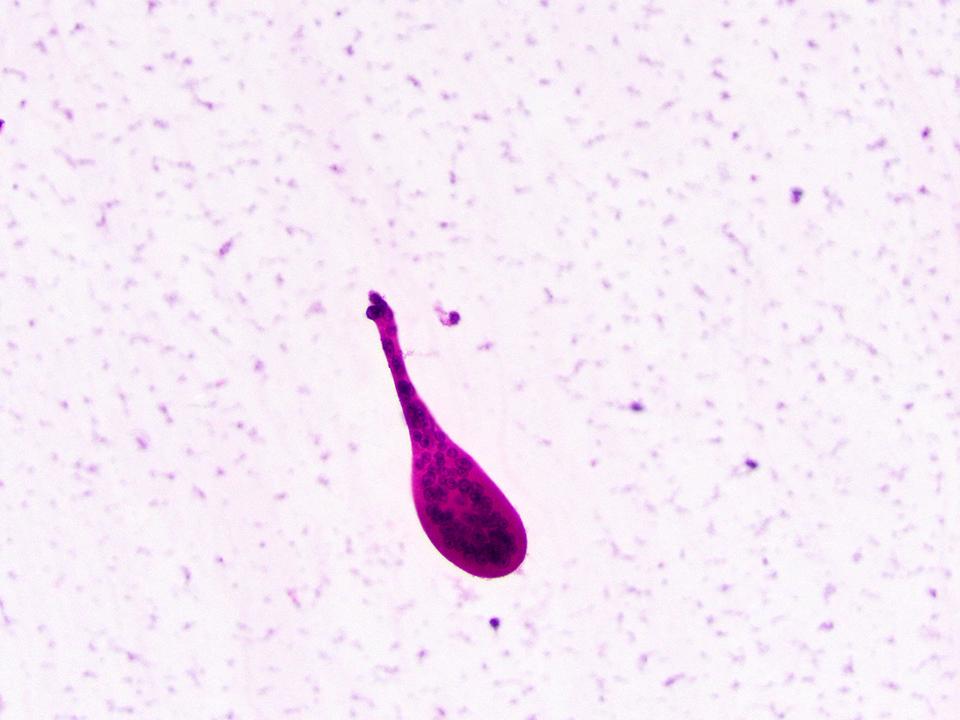

Microscopic (histologic) images

Contributed by Chrystalle Katte Carreon, M.D. and Drucilla J. Roberts, M.D.

Cytology description

- Although not routinely performed, cytologic analysis may, on some occasions, aid in the identification of rare trophoblast cells, which supports the clinical impression of intrauterine pregnancy